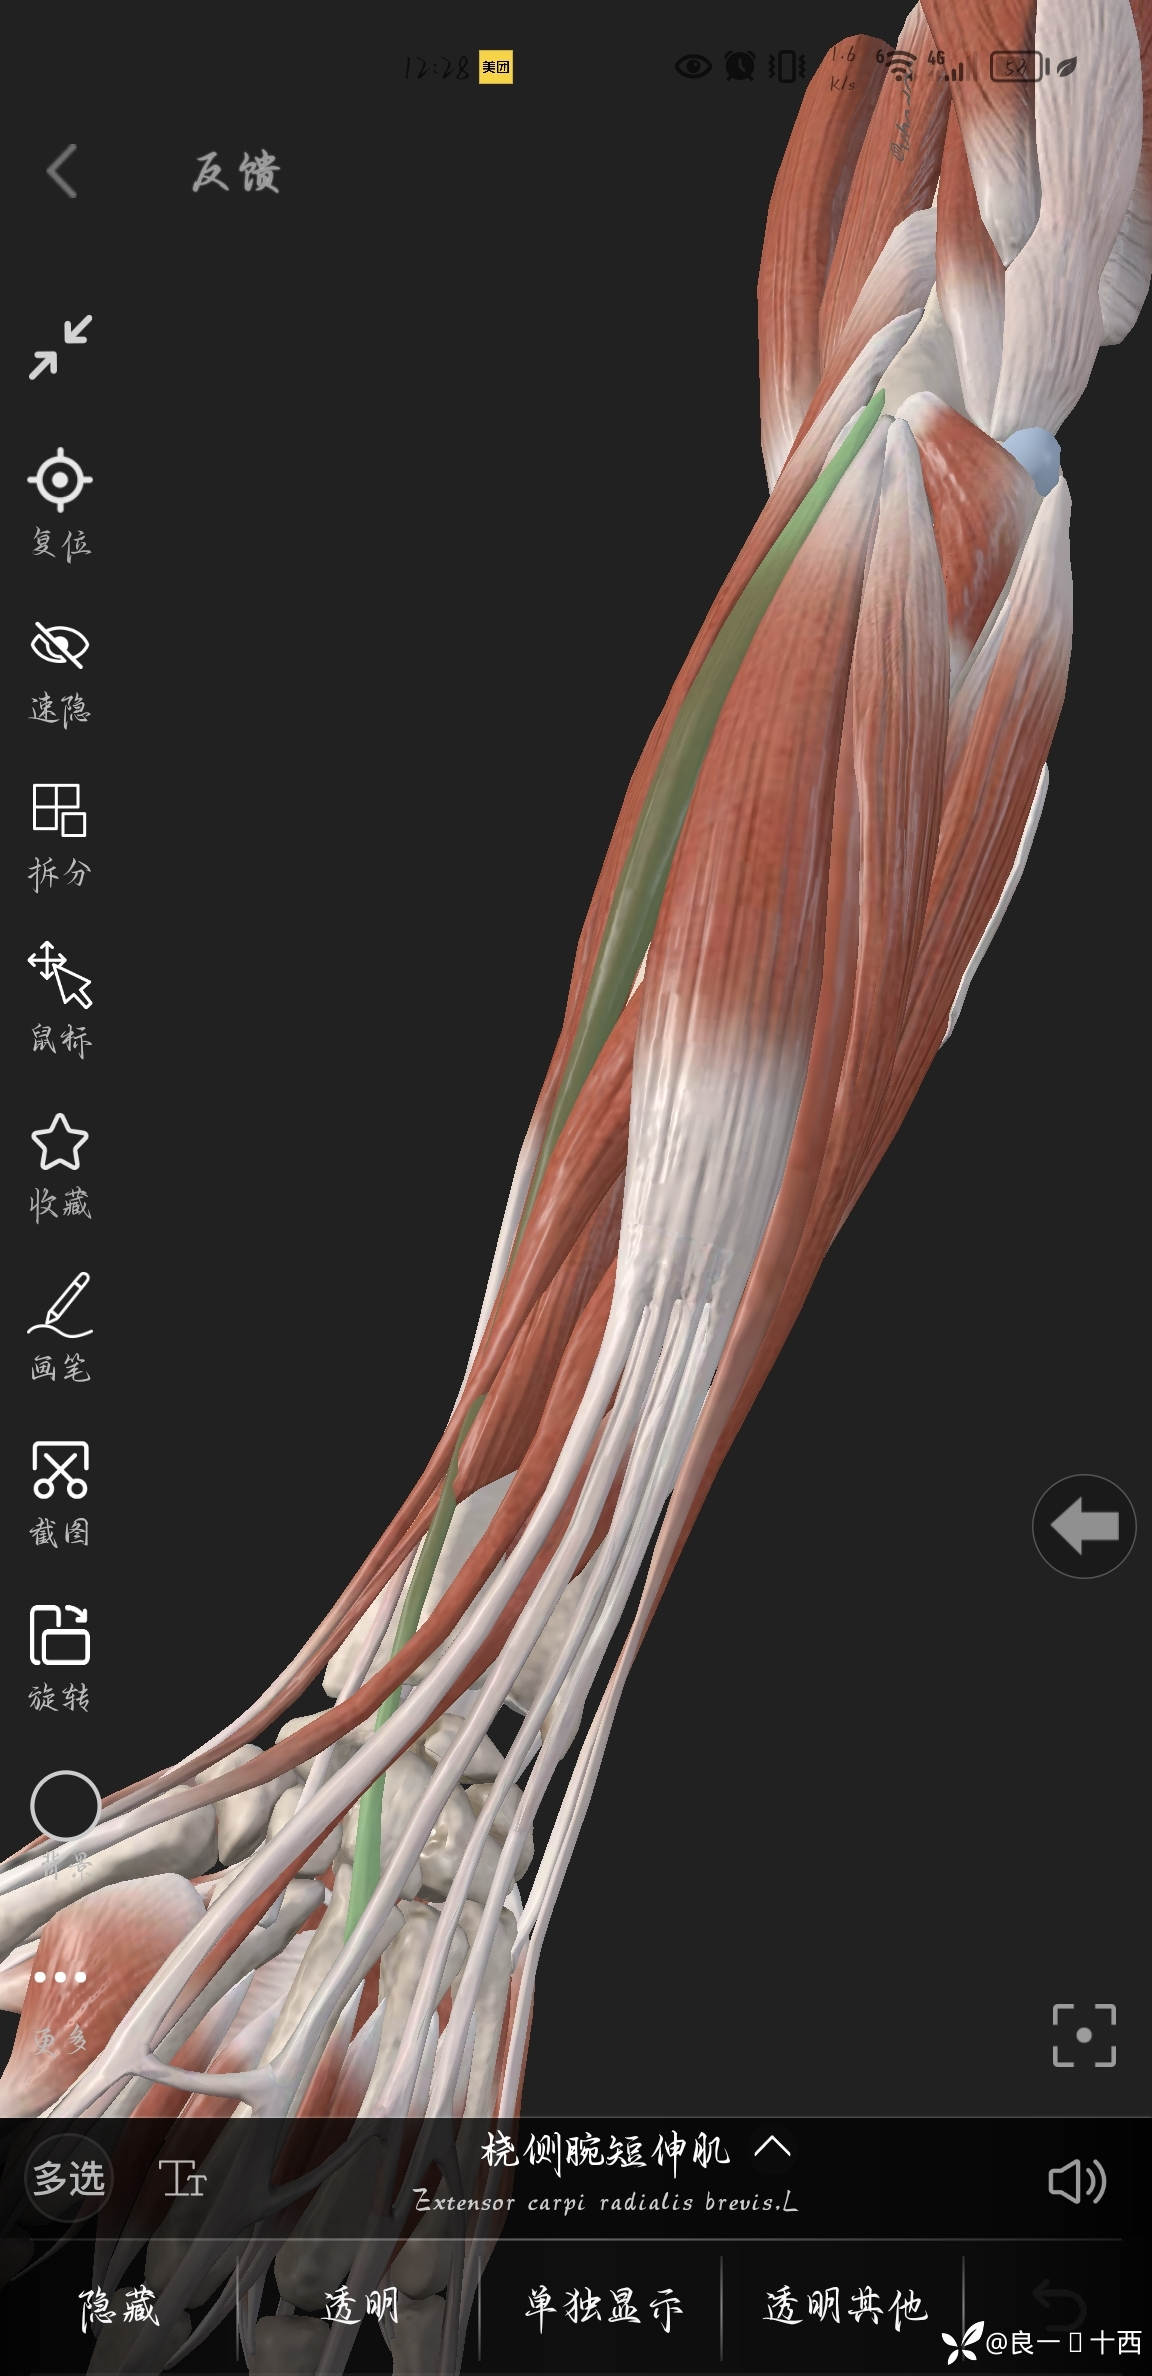

断裂的两根肌腱及位置如下图所示

一开始想从鞘管两段里面用止血钳看看能不能把断裂回缩的肌腱给拉出来,减少创伤,可是试了二十来分钟,也没有全部拉出来,得嘞,沿着鞘管纵形切开,终于是各自找到了断裂的桡侧腕长伸肌腱跟桡侧腕短伸肌腱,松一口气,把心里的石头放下了肚子里,使用缝线标记。